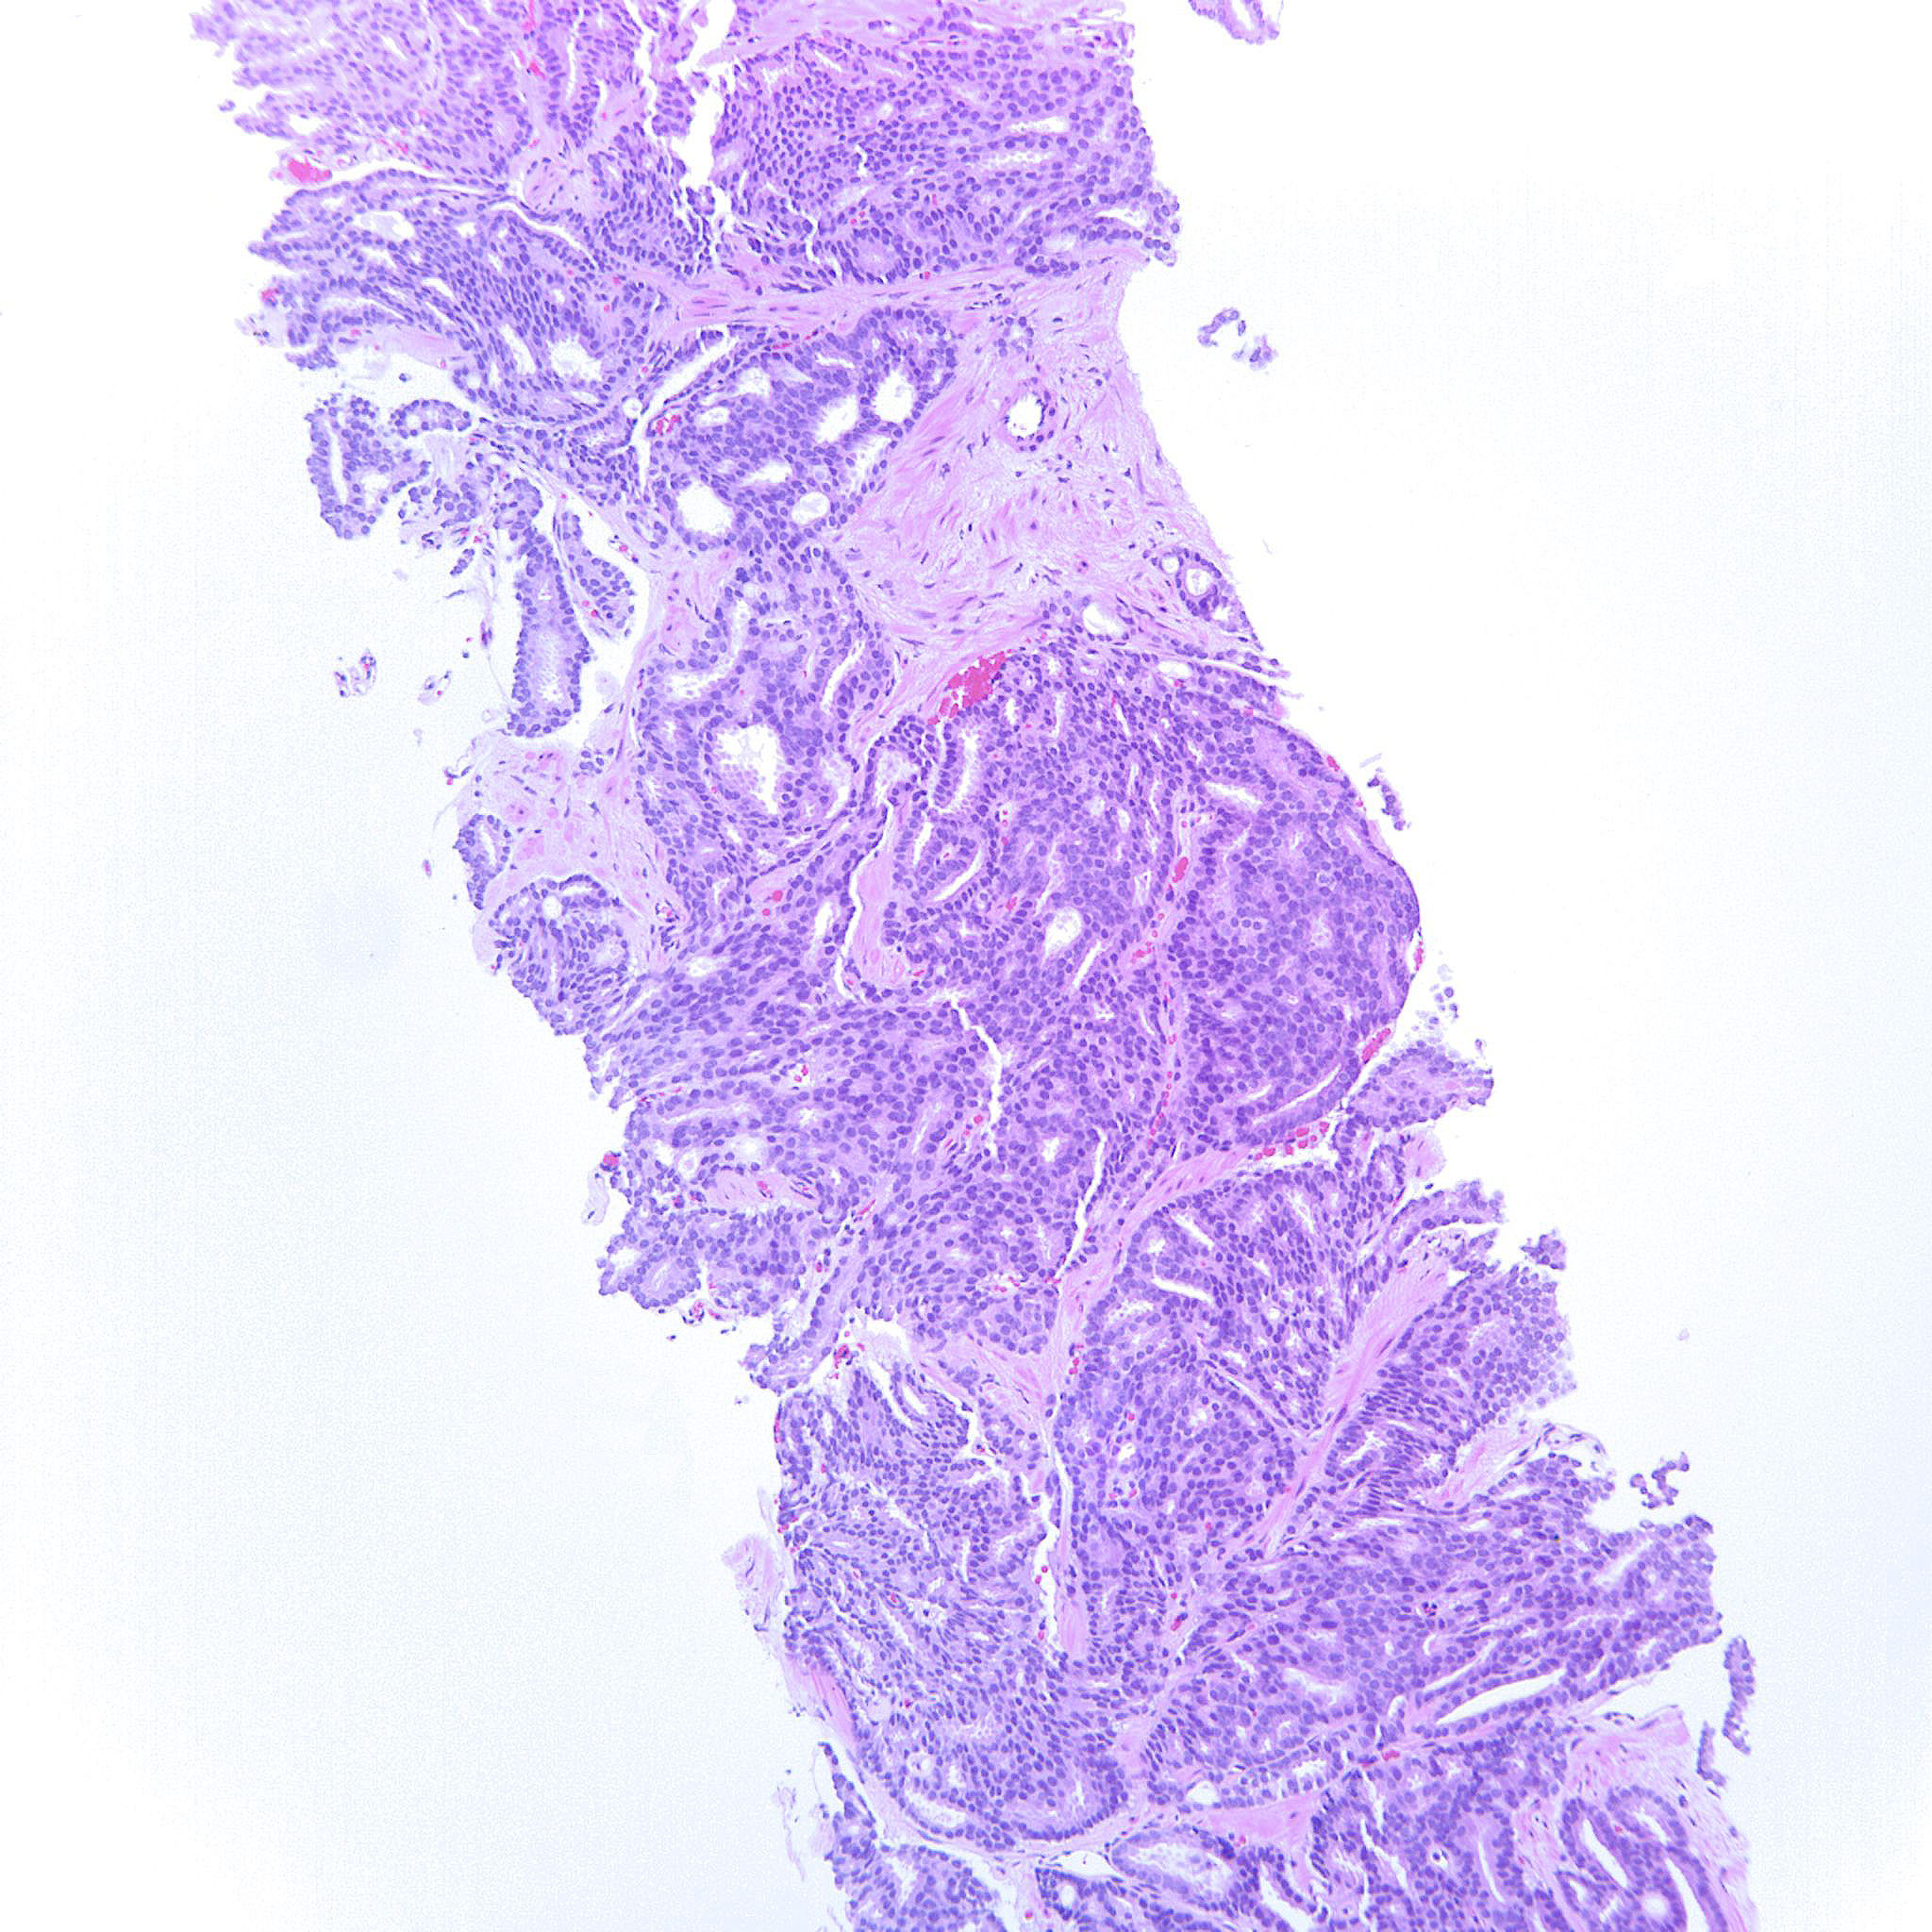

Prostate cancer grading

Case ID: 227